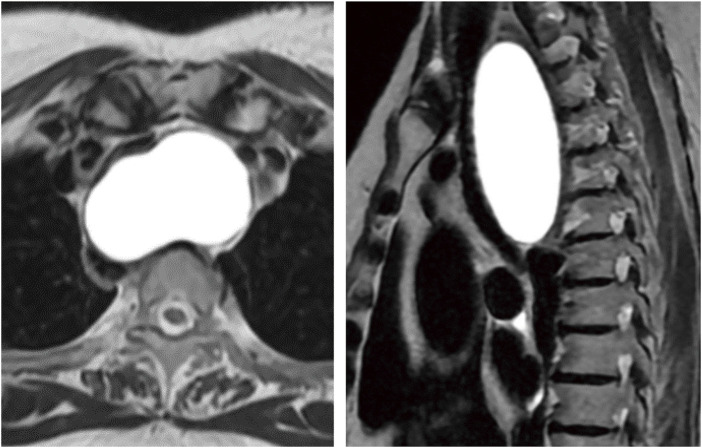

Case presentation: A 64-year-old woman with exertional dyspnea was diagnosed with a superior mediastinal cyst compressing the trachea and esophagus. Preoperative EUS-FNA was performed to reduce the cyst volume and any mitigate potential complications during anesthesia induction. Three days later, she developed dyspnea due to a delayed intracystic hemorrhage, necessitating emergency surgery. VATS with a confronting upside-down monitor setup was performed under standby V-A ECMO. Despite a limited surgical field under 2-lung ventilation, a confronting upside-down VATS approach allowed sufficient visualization and maneuverability. The patient had an uneventful recovery, with no recurrence at 3 months.